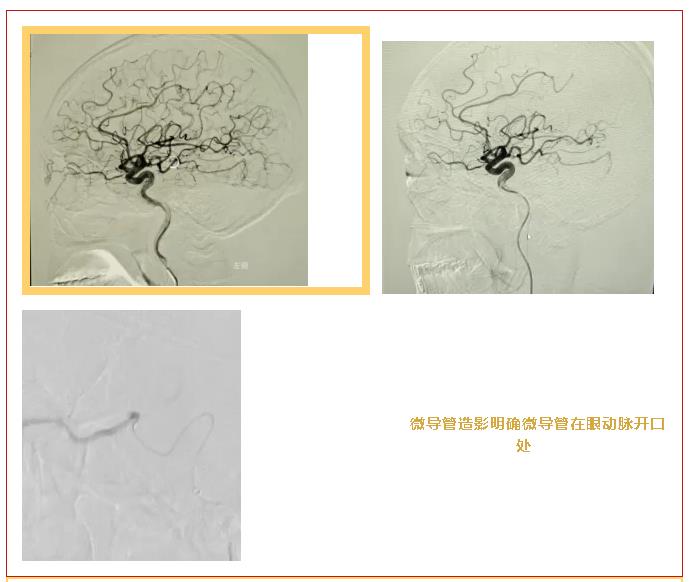

传统的扩张血管、降低眼压等保守治疗,对视网膜动脉阻塞的救治效果收效甚微,而超选择性眼动脉介入溶栓术是目前国际上证实的治疗该疾病的首选方案。手术中,神经外科专家精准完成股动脉穿刺、微导管置入操作,结合脑动脉造影实现眼动脉阻塞部位的精确定位;介入室团队为血管介入操作提供专业技术支撑,全程保障术中血管通路安全;眼科团队实时监测患者眼部体征,精准把控溶栓药物剂量与注射节奏。三大学科紧密协同,将仅0.014英寸、约头发丝粗细的超选择性微导管,精准送达患者左眼动脉栓塞部位,缓慢注入溶栓药物,实现血栓的精准溶解与血管的有效再通。整个手术微创、顺利完成,相较全身静脉溶栓,该术式将药物直接作用于栓塞靶点,大幅降低颅内和全身出血风险,真正实现了靶向溶栓、高效低险的治疗目标。